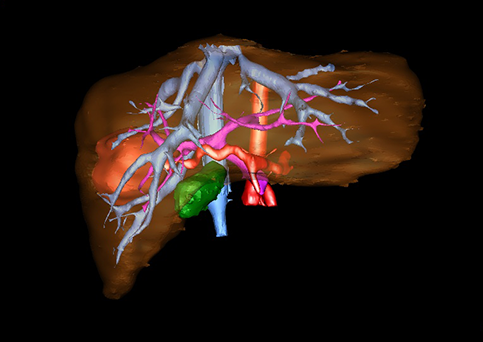

近年来由于数字医学的发展,基于可视化三维重建技术的计算机辅助手术系统极大推进了小儿肝脏肿瘤的精准手术的进步。可以立体透视肝脏解剖、精确掌握肝段的边界、精确测算肝段乃至任意血管所支配的功能体积、准确定位病灶及其与邻近血管的解剖关系,最终对不同手术方案进行比较、筛选和优化。因此,计算机辅助手术规划系统是实现精准肝切除的有力辅助工具,是未来数字外科、精准外科等21世纪外科新理念的重要技术支撑。

计算机辅助手术规划系统具有良好的操作可行性、计算准确性和三维显示效果,可半透明、交互式显示真实的肝内立体解剖关系和空间管道变异,准确计算肝内管道的直径、走行角度,两点间的垂直距离,和任意血管的支配或引流范围等传统二维影像无法获取的信息,有助于实施个体化手术,提高了手术的确定性、预见性和可控性。计算机辅助手术规划系统可直观显示预留肝脏的结构和功能,并可通过虚拟切割功能辅助术者对手术方案进行蹄选和优化,系统评估手术风险和制定对策,改变了部分二维规划的术式和切除范围,使部分二维规划认为不能切除的患者成功手术,提高了手术的根治性、安全性和病变的可切除性,更加符合精准肝脏外科的术前规划要求。详见第11章。

为了更便利地指导床应用,目前国际上肝胆外科的临床医生多采用肝脏Couinaud分类方法。该方法主要以肝门静脉的走行为分类基础,将右前叶分为上下两段,即肝脏分为8段:尾状叶为第Ⅰ段,左外叶分为Ⅱ、Ⅲ段,左内叶为第Ⅳ段,右前叶分为第Ⅴ、Ⅵ段,右后叶分为第Ⅶ、Ⅷ段。了解这些肝脏的分叶和分段法,对于肝脏疾病的定位和手术中血管、胆管系统的正确处理都具有重要的指导意义。见图22。

随着计算机技术及影像检查技术的不断发展,以精确的术前影像学和功能评估、精细的手术操作为核心的精准肝切除技术日益受到重视。基于数字医学的计算机辅助手术技术(computer-assisted surgery,CAS)则是实现肝脏精准手术操作的基础。计算机辅助手术系统(CAS)可将术前二维(two dimensional,2D)的CT/MRI影像数据进行三维(three dimensional,3D)重建,建立个体化的肝脏三维解剖模型,清晰显示肝脏内脉管系统的走行及解剖关系,还原病灶与其周围脉管结构的立体解剖构象,准确地对病变进行定位、定性和评估,制定合理、定量的手术方案,实施个体化的肝脏血管取舍分配方案及实施精准肝脏手术。一般认为CAS包括:创建虚拟的患者的图像;患者图像的分析与深度处理;诊断、手术前规划、手术步骤的模拟;术中实时导航。应用本技术后,由于可以更清晰地看出肿瘤的界限,特别是根据肝血管的显影,判断出肿瘤与门静脉及肝静脉的关系以在手术前较准确地估计出手术成功切除的可行性。以往部分根据普通强化CT判断无法手术的病例而被评估为可以成功切除并手术成功。